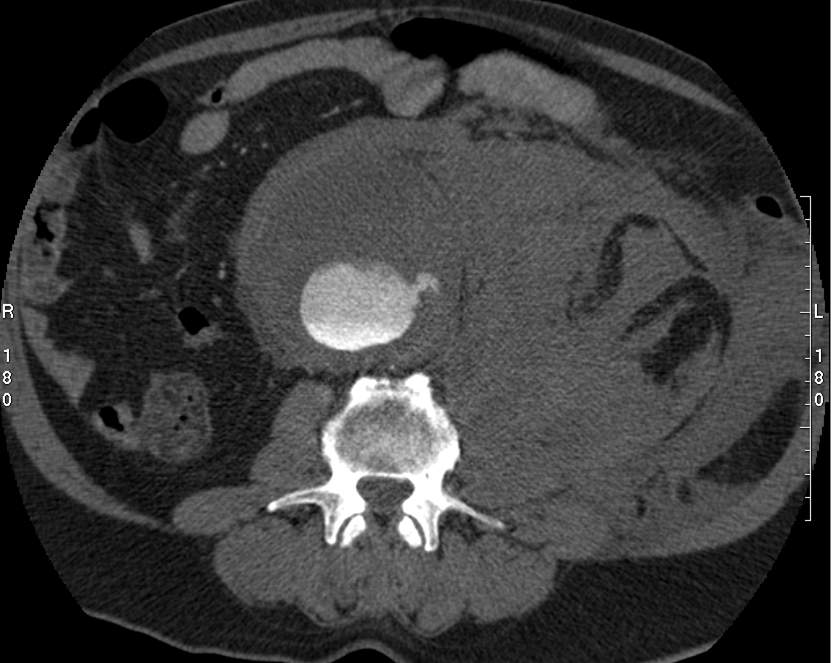

Image

A non-ruptured (stable) aneurysm with an extended mural thrombus

Ruptured aneurysm with retroperitoneal hematoma

Fig. 24., 25.: Abdominal aorta aneurysm, CT angiography